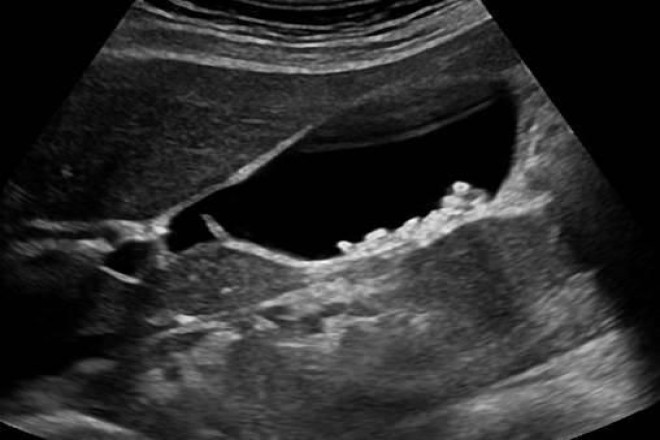

Criterios ecográficos de la colecistitis aguda

• Grosor de la pared vesicular igual o mayor de 4 mm

• Presencia de edema de la pared vesicular

• Litiasis intravesicular proyectada en el cuello

• Tamaño superior a 100 x 60 mm

• Líquido perivesicular, colédoco dilatado y bilis de estasis

Se establecen los criterios ecográficos diagnósticos para este padecimiento, como el grosor de la pared vesicular, la presencia de edema de la pared vesicular, litiasis intravesicular proyectada en el cuello, tamaño superior a 100 x 60 mm, líquido perivesicular, colédoco dilatado y bilis de estasis.